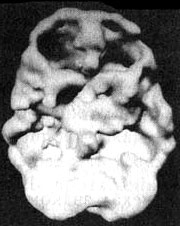

На иллюстрации — мозг сорокадевятилетнего пациента, который вдыхал пары токсических веществ на протяжении 12 лет. По своему виду этот мозг сильно напоминает мозг, пораженный кокаином или метамфетамином.

Мозг токсикомана

Трехмерное изображение поверхности, вид сверху. Обратите внимание на обширные «провалы» активности на всей поверхности мозга.